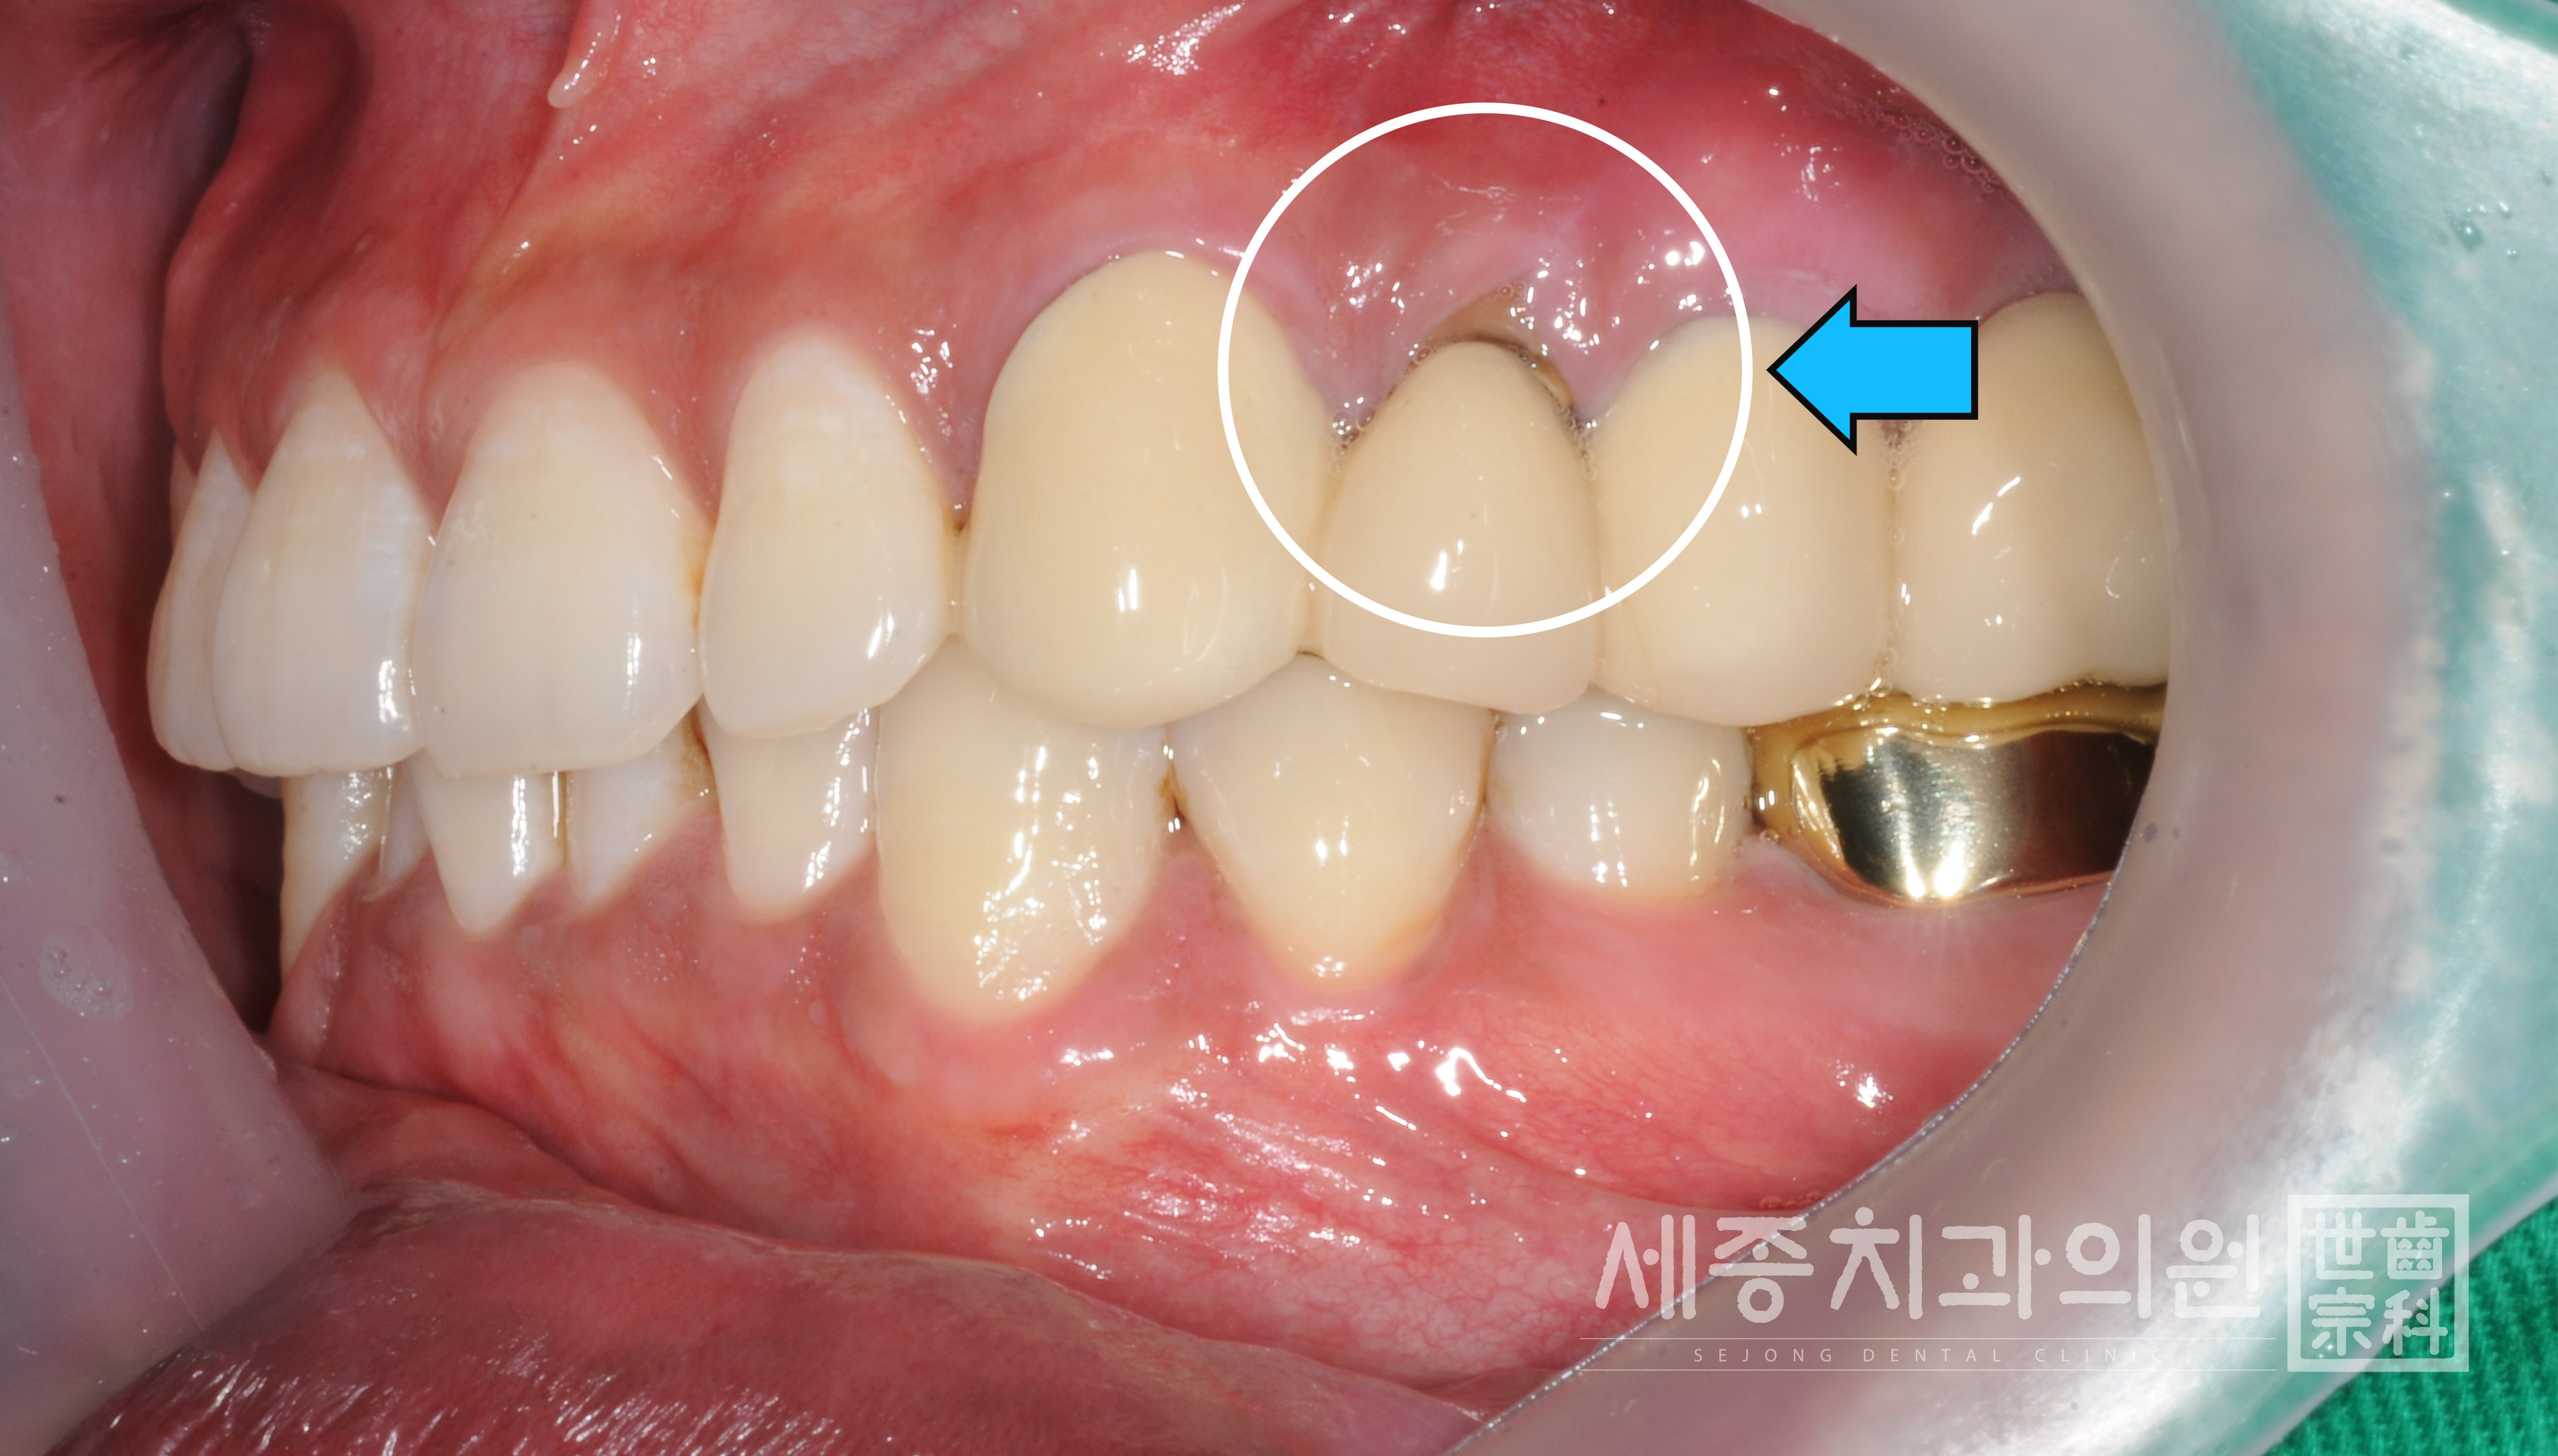

40대 부산임플란트잘하는곳 세종치과 환자분의 경우에도 잇몸이 부어 있고 마진이 생긴 것을

확인할 수 있었습니다.

보철물과 잇몸의 경계 부분은 '마진'이라고 합니다.

보철물을 딱 맞제 제작하더라도 시간이 지나 잇몸이 내려가면서 마진이 생길 수 밖에 없는데요.

마진 틈으로 세균이 침투해 충치와 염증이 생기게 됩니다.